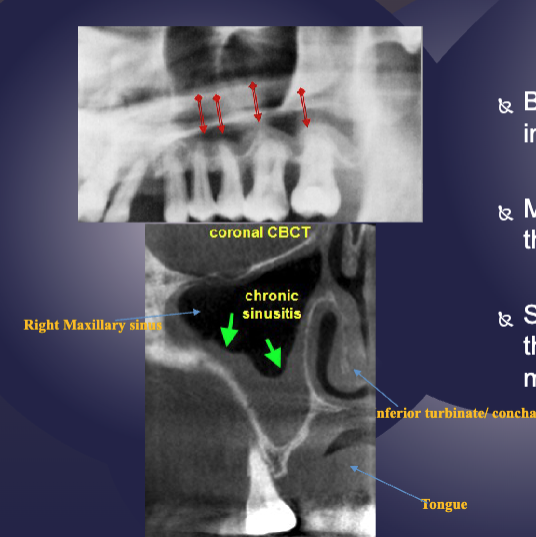

what’s the pathology

floor of max sinus elevated/displaced → rarefying osteitis

sinusitis + mucositis in max sinus are shown radiographically via

sclerotic changes in boney walls